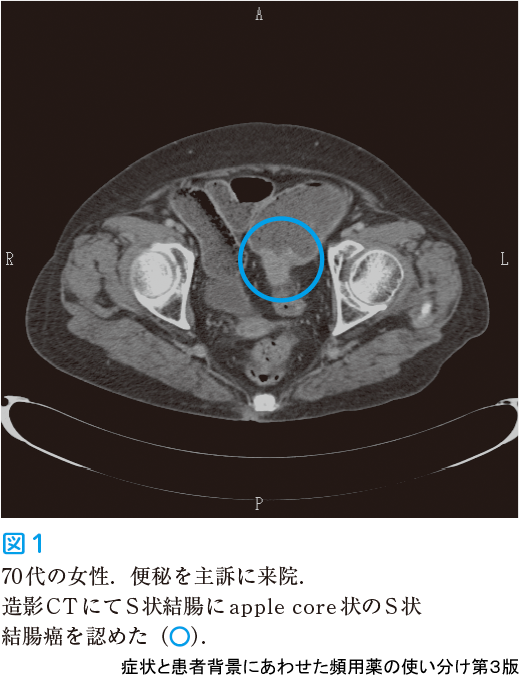

次に使用薬剤の把握,血液検査やX 線検査,便潜血検査を行います.便潜血検査が陽性の場合は下部内視鏡検査を行います.何と言っても見逃してはいけないのが悪性腫瘍ですが,便秘をきたすほどの腫瘍がある場合,X 線やCT 検査で腸管狭窄や腫瘤として捉えられることがあります(図1).血液検査では電解質,血糖値,甲状腺ホルモンなどの検査を行い内分泌疾患に続発する便秘の除外を行います.